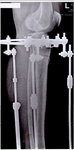

ножки в аппаратах, в день снятия.